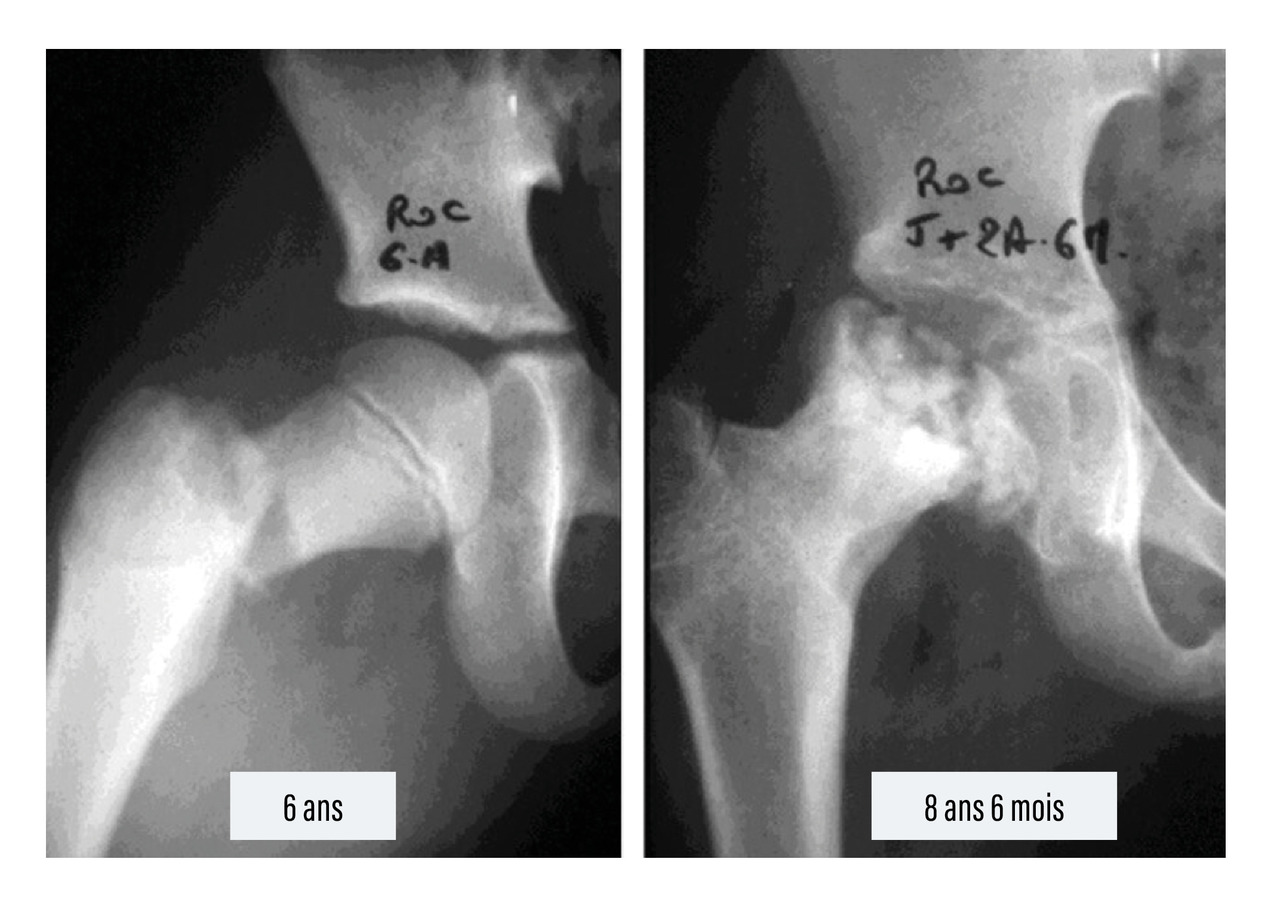

• les nécroses épiphysaires par lésions ischémiques, qui concernent surtout la tête fémorale, après fracture du col15 (fig. 11), la tête radiale et le condyle externe du coude ;

• les raccourcissements et les désaxations des membres par atteinte du cartilage de croissance (épiphysiodèse) ;16